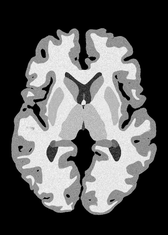

4.2 Registration to a 100 micron ex-vivo brain MRI volume

To showcase the efficacy of our method on real large scale images, we register a 250 in-vivo MRI image (Lüsebrink et al., 2017) to a 100 ex-vivo FLASH human brain volume (Edlow et al., 2019). This represents an inverse problem with more than 11.2B optimizable parameters (compared to 20M for clinical datasets), or 44.8GB of GPU memory. The entire problem does not fit on most GPUs, necessitating distributed multimodal registration. We optimize a composite transform - affine followed by a diffeomorphic mapping; details can be found in Section E.1. Multimodal deformable registration took 58 seconds on 8 NVIDIA A6000 GPUs, which is unprecedented at this resolution. Fig. 6 shows qualitative results, highlighting the ability to register highly detailed structures such as cerebellar white matter; these structures are not visible at macroscopic scales. The resultant advantages of performing registration at this scale can allow researchers to characterize the neuroanatomy at microscopic resolutions and allow morphometric analysis of cortical layers and subcortical nuclei among other structures.